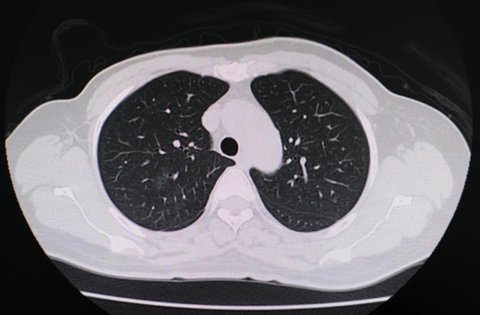

2024-07-23在醫(yī)學(xué)影像上,所謂的“白肺”通常指的是肺部出現(xiàn)廣泛炎癥的情況,這可能是由重癥肺炎、ARDS或其他嚴(yán)重的肺部疾病引起的。了解這些癥狀對(duì)于早期診斷和治療至關(guān)重要。